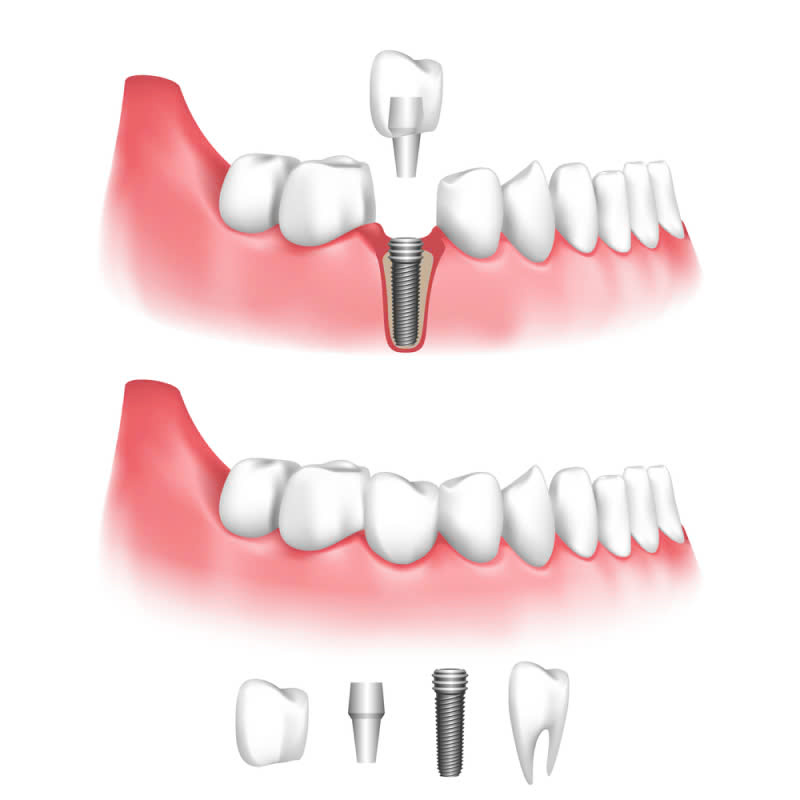

Trồng răng implant là một trụ kim loại, thường được làm từ titanium, được cấy vào xương hàm để thay thế chân răng bị mất. Trên trụ implant, bác sĩ sẽ gắn mão răng sứ hoặc các loại mão răng khác để phục hồi chức năng nhai và thẩm mỹ của hàm răng.

Bác sĩ sẽ tiến hành cấy ghép trụ implant vào xương hàm, sau đó khâu vết thương.

Sau khi trụ implant liền xương, bác sĩ sẽ tiến hành lắp mão răng sứ lên trụ implant.